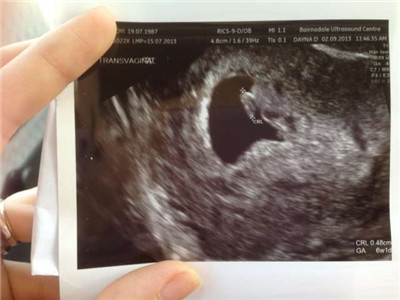

通过检查孕囊的大小,是无法确定胎儿的性别的。

怀孕之后通过超声检查是可能知道胎儿的大小的,看婴儿性别最准确的方法是检查染色体。但是只是单纯从孕囊的大小还是无法知道的。

1、看孕囊的长宽是不能知道男女的,当胎儿在孕5个月以上,外生殖器开始发育后,在彩超下有可能看到是男孩还是女孩,但如果有身体或肢体的遮挡也有可能是看不清楚的。孕囊的长宽推测胎儿性别是没有依据的。